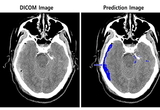

• SK㈜ C&C ‘뇌출혈 판독 AI모델’ GMP 인증..기대 효과는?